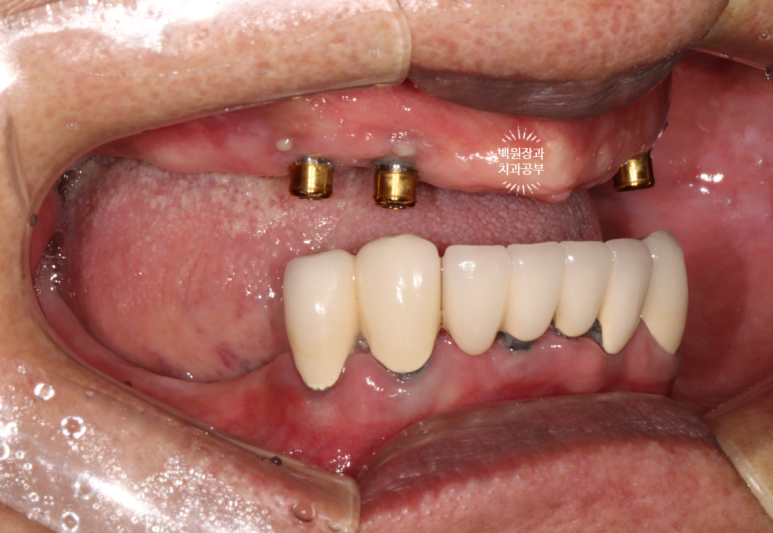

금색의 locator가 장착된 임플란트의 주변에 고름이 맺혀있는게 보이시나요..?

네개의 임플란트 모두 상당한 임플란트주위염에 시달리고 있는 것을 볼 수 있었습니다.

위턱은 임플란트를 모두 제거한 후 임플란트 없이 완전틀니로,

아래턱은 치아를 모두 제거하고 임플란트틀니로 계획했습니다.

임플란트를 2개만 심고 오버덴쳐를 하기로 하였습니다.

그러고 보니 위아래가 바뀌게 되었네요 !! 사실 이게 교과서적인 치료입니다.

임플란트 주위 치주염에 걸려 고름이 나오면서 빠지기 직전이었던 위턱 임플란트 4개는 모두 제거하였고,

치아우식증과 치주염에 이환된 아래 치아들도 모두 발치하고, 2개의 임플란트를 새로 심어드렸습니다.!!!